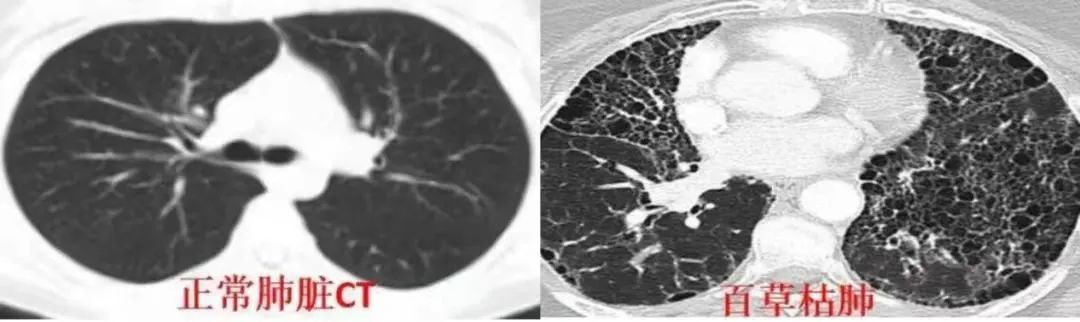

依据过往的新闻案例,服下百草枯的人,生还几率极低。这是一种“给人后悔的时间,不给人后悔机会”的剧毒农药,可致死剂量小至10毫升,甚者仅仅含在口腔中都可能导致中毒,服毒者的生还概率可能小至千分、万分之一。

致命“感冒药” 事情是在2021年深冬发生的。 12月初,正念高三的萌萌因为课业压力太大,情绪不振,母亲高娟心疼女儿,便给萌萌请了几天假在家休息。 5日,萌萌的姐姐因事不能在家照看孩子,便拜托妹妹前去帮忙。 那是再平常不能的一天,离开家时,萌萌桌上的书还是翻开的状态,“谁能想到会出事呢?”母亲高娟在采访里哭着说道。 然而,在姐姐家的当天晚上,姐夫陈某忽然以“预防感冒”为由,劝说萌萌服下一种“感冒冲剂颗粒”。彼时,萌萌一口饮下后就觉得味道奇怪,当场就吐了,但姐夫万般劝说,后来还是喝完了两杯“感冒药”。 萌萌被投毒入院 这天过后,萌萌的身体出现了一些糟糕的反应。她上吐下泻,萎靡不振,吃药、输液都不见效,甚至反而加剧症状,到威县医院去检查,也未能查出病因。 12月27日,家人将萌萌送去河北省人民医院检查,尿检结果显示,萌萌体内检测到浓度为70ng/mL的百草枯。 河北博睿医学检验实验室的毒物检测报告单(图源:极目新闻) 身为农人,萌萌父母比谁都更清楚百草枯的危害性。他们瞬息崩溃,紧接着是不解和疑惑:女儿为何服下了剧毒农药? 原来,5号那天晚上姐夫给萌萌喝下的“感冒药”,就是被稀释后的百草枯。 百草枯的药性是延后生效的,服药足足12天后,百草枯真正的危害性才开始在萌萌体内迅速蔓延。 这期间,肺间质纤维化、呼吸衰竭、肝肾损伤等等恶果会先后发生。很快,萌萌被送进重症监护室,每天医药费高达2万元。 萌萌在医院(图源:南方都市报) 在省人民医院住院的半个月,萌萌父母从未离开女儿。每天早晨,高娟看着一根长长的管子插进萌萌口腔中,通过人工加压将食物运送到萌萌食道与胃部,她看不得女儿遭罪,不止一次想过“让我来替妮儿受这罪吧”。 百草枯的另一大特点,是对人体中枢神经的侵害较小,这意味着,当人体的所有器官逐渐被腐蚀、衰竭时,人的头脑意识却是清醒的。 住院初期,萌萌还会与父母讲话,她告诉母亲,“俺不想死,我想活,我还想去旅游,看看雪,看看水。” 1月6日,萌萌转院至北京解放军总医院,被告知需要进行肺移植手术,彼时,据众筹平台公示,其家属筹款目标调至100万,当时已筹款49.6万。 萌萌的水滴筹目前已筹到约55万元 但器官移植最大的阻碍尚不是费用问题。百草枯对人体的损蚀是全方位的,即便成功完成肺移植手术,女孩体内的其他器官是否亦能恢复如常? 缘何下毒手 得知是姐夫下的毒时,萌萌一家人都感到很意外,萌萌父亲马东涛在接受采访时直言,“平常我跟我女婿没什么矛盾”,对一切毫无预料的萌萌姐姐也无助地表示,“我就不知道他为啥这么狠心”。 萌萌父亲马东涛接受采访(截图:微博@农民频道) 很快,警方展开调查并锁定、拘留了嫌疑人陈某。据威县公安局的警情通报:犯罪嫌疑人自感家庭经济条件差,其岳父一家“瞧不起自己”,遂产生报复心理。 可后来马东涛坚决否定了这一点。在他的讲述里,大女儿与女婿结婚四五年,育有一子,两人平时“感情很好”,马家对女婿也不错,逢年过节都会走动,根本不存在瞧不起一说。因此,马东涛认为,“瞧不起”只是投毒者的借口。 据“百姓关注”视频报道,萌萌的姐姐马燕称,5日当晚,萌萌在自己家中单独睡一个卧室,而马燕自己因为上班较累,带着孩子很早就在另一个房间睡着了。 深夜,丈夫陈某“硬逼着让孩子(萌萌)喝药,他也没开灯”,并坚称是治感冒的药。后有亲戚分析称,也许因为是在别人家,不好拒绝,萌萌就喝下了这来历不明的药水。 萌萌的姐姐在视频中描述萌萌喝百草枯经过(截图:微博@农民频道) 马燕至今不能理解丈夫的行为,在她的讲述里,家人都很疼爱陈某,常给他做好吃的,“他来我家爱吃肉,我妈就给他做”。 马燕表示,“我愿意依法惩治他,不愿意再看到他”。 陈某的父亲也对儿子的所作所为表示了不理解和愧疚,他自称觉得很对不起萌萌一家,曾恳求社会各界人士救救“我们家萌萌”。 好消息是一夜之间来临的,公众的祝愿与忧虑,女孩家人的竭尽全力没有白费。 在爱心人士的捐献下,1月6日晚上,肺源通过器官转运的绿色通道抵达了北京。6日晚10点半,被誉为我国“肺移植第一人”的医生陈静瑜连夜从无锡赶到北京参加会诊,并当即开展移植手术。 陈静瑜医生从无锡赶到北京为萌萌进行手术(图源:微博@陈静瑜肺腑之言) 肺部上连气管,下通心腔,通流着无数关键神经与血管,双肺移植的风险可见一斑。 手术顺利完成后,陈医生在微博表示称,正是由于我国近年来逐渐发展成熟的脑死亡爱心捐献,通过国家供体网络分配系统的分配,萌萌才能得以在短期内得到了爱心捐献的肺源。 但这依然带来了巨大的惊惧与颤抖。 公开报道过的服百草枯生还者屈指可数,最典型的如2013年服毒半个月后康复的“杀鱼弟”孟凡森,因为抢救时间及时,才能在即便服下超过15ml致死量后仍被成功救治。 “杀鱼弟”孟凡森因喝百草枯入院(图源:中新网) 距服药整整12天后才被送医诊断的萌萌,无疑错过了最佳抢救时间。 谁也无法体会在这12天内,女孩经历了多么惨烈的折磨。 错的不是药 百草枯是一种由吡啶、金属钠、硫酸二甲酯反应而成的除草剂,最早由英国帝国化学工业集团研发,1962年投放市场。但当时百草枯的价格昂贵,普通中国农民无法承担。 2003年,我国科学家李德军通过8年的潜心钻研,成功制作出百草枯成品并投入量产,足够便宜、好用,且因为遇土失活,并不会给环境带来污染。 李德军(图源:人物) 然而,一旦进入人体,其致命性是一般农药遥不可及的。 对于这种剧毒农药,在各类新闻和科普中,有至少两点特征几乎已成为常识: 其一,是百草枯发效的延迟性。 百草枯对人体的超高致命性,主要来自于不可逆的肺间质纤维化。然而,由于其主要靶器官是肺,短期内并不会出现严重的症状。因此,大部分患者在中毒初期难以意识到自己身体内出现的变化。 当毒性开始生效,百草枯渗入口腔黏膜,口腔内开始溃烂,伴有血性渗出,咽部红肿、扁桃体肿大。患者开始感到说话困难,疼痛难忍,同时,胃黏膜在灼伤下也会引起胃痛。 萌萌喝百草枯后舌头被烧伤(截图:微博@农民频道) 紧接着,肺部随着逐渐纤维化功能越来越差,患者会感到呼吸费力,出现急性肺损伤(ALI)或者急性呼吸窘迫综合症(ARDS)、全身多器官功能不全综合症(MODS),直到肺泡内和肺间质纤维化,最终致人呼吸衰竭而死。 换句话说,百草枯中毒且未能生还者,几乎都是“憋死”的。 第二个特征,是百草枯侵蚀全身器官,却独独不会严重损害中枢神经系统。这也意味着,以上列举的所有症状,都是患者在神志清醒的状态下能清晰感受、意识到的。 这是一种身体和精神的双重摧毁,是一个堪比极刑的过程。 更可悲的是,迄今为止,百草枯尚未出现有效解药,医学能做的只是减轻痛苦,减慢病程,从死神那里争取时间,到头来,不少患者往往人财两空。 正常肺脏和百草枯肺对比(图源:医学界) 在新闻报道里,服下百草枯的患者大多是出于自杀欲图,但即便是为求结束自己的生命,服下百草枯的人,大多对这种毒药的程度了解不深,或当作普通毒药,期待“一击致命”,服下后的漫长痛苦,才会带来必然的后悔。 2021年10月,怂恿网络主播“罗小猫猫子”服百草枯继而导致年轻生命消亡的网友,虽然从法律上难定其罪,但在道德与伦理上或与施毒者其状相类。 主播@罗小猫猫子服百草枯去世 近年来,随着百草枯自杀者个案时有出现,百草枯逐渐淡出国内市场。2014年7月1日起,我国撤销百草枯水剂登记和生产许可、停止生产,但保留母药生产企业水剂出口境外登记、允许专供出口生产;2016年7月,停止其在国内销售和使用,2020年,国内市场上流通的最后一批百草枯有效期到期。 对于百草枯的名声渐变致命,“百草枯之父”李德军倍感痛心和愧怍,目前,李德军有迹可循的最后一次公开发声,是在2016年《经济观察报》的一次采访里,他失落地说:“说实在话,百草枯我感觉是很得意的一个作品,是我一生科学研究工作里最得意的一个作品……没想到这么得意的作品上面出现了这么严重的瑕疵,对这个问题我很惭愧……就像自己的孩子,原本养大了感觉挺有出息的,最后不行了,确实心理是不好受。” 百草枯的功与过仍然存留着争议,但纵观近年来屡屡登上新闻头条的各种事件,网友们的声音有着一定道理:“有罪的不是药,是人。” 编辑 | 莫奈 排版 | 菲菲